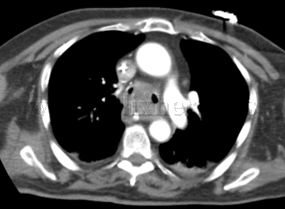

Neoplasia de carina principal